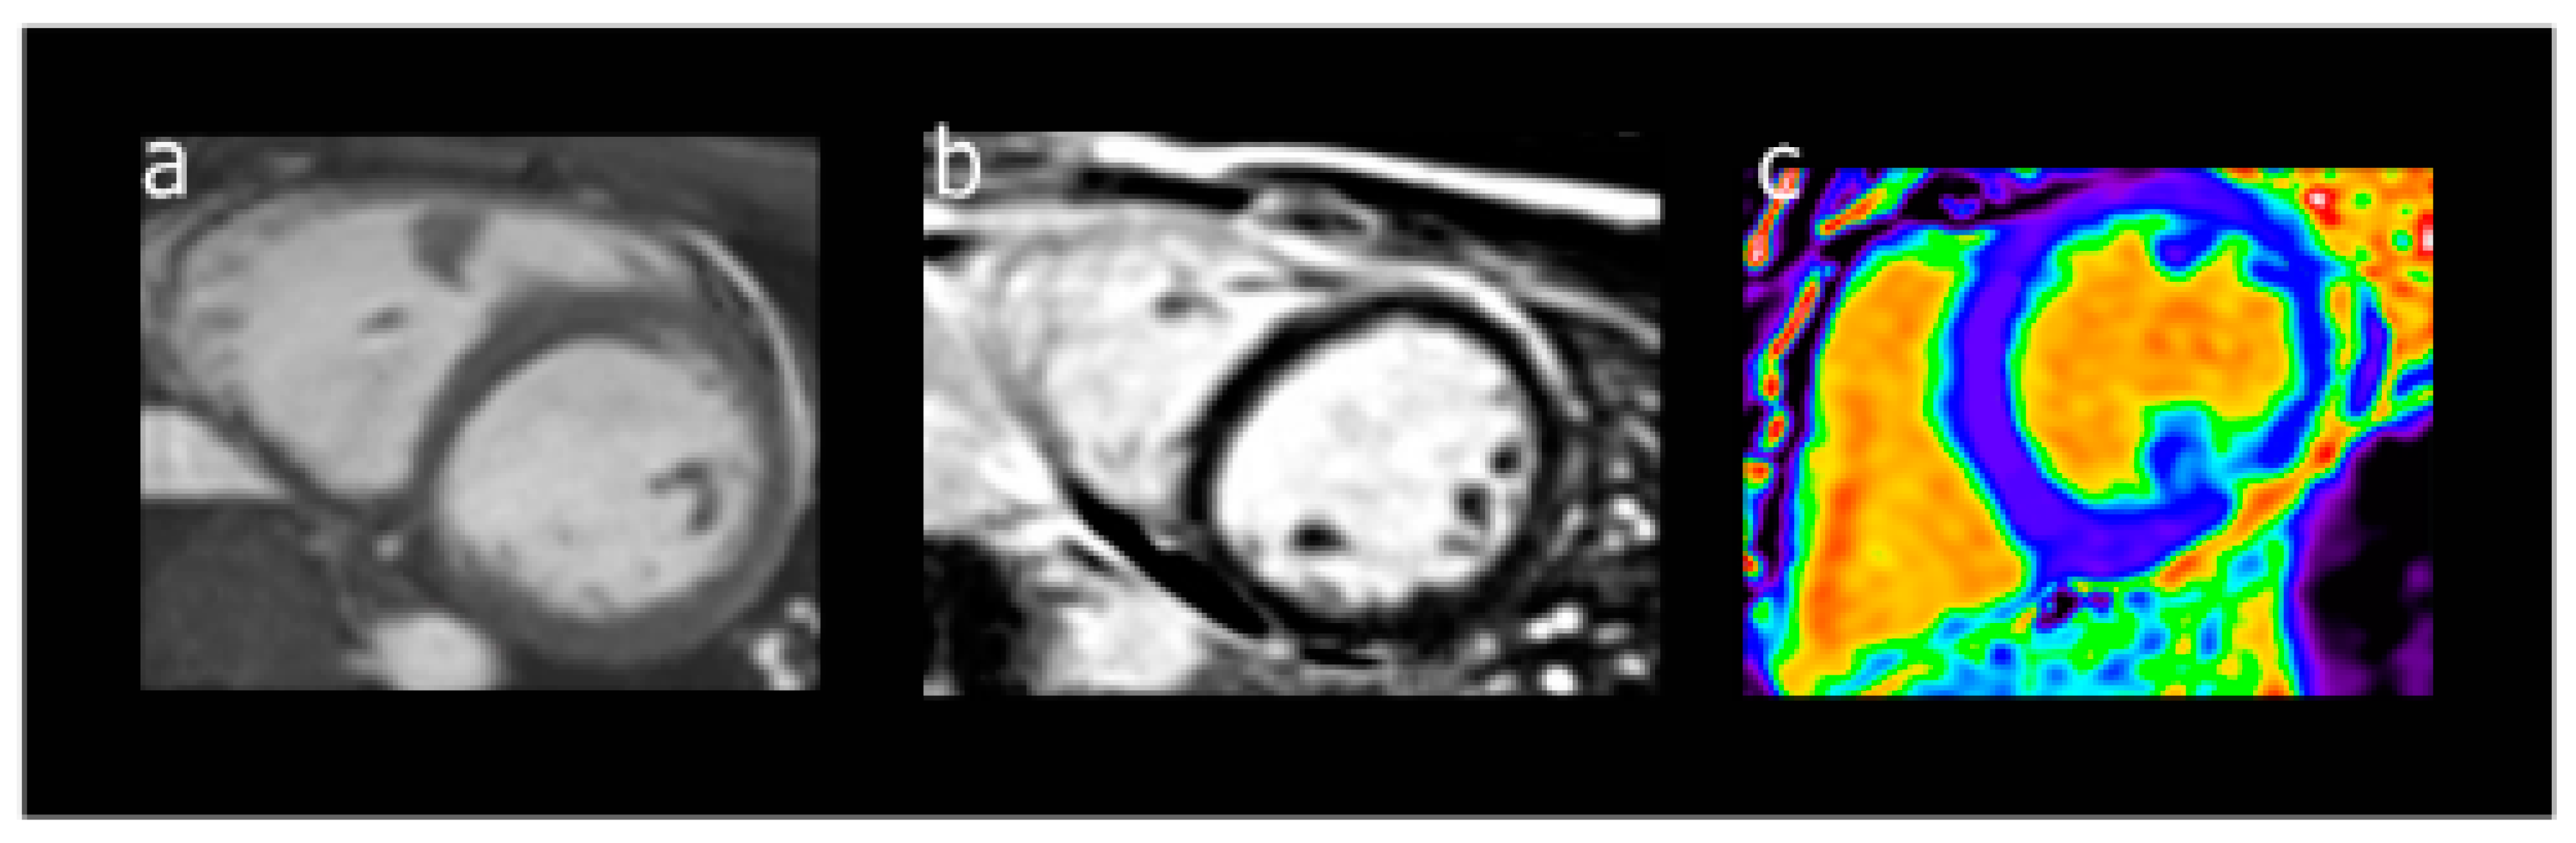

Cardiac magnetic resonance (CMR) imaging is not yet common in clinical practice but is emerging as an important monitoring tool for cardiomyopathy. CMR provides better structural imaging and more accurate measurements of systolic function and myocardial tissue characterization. Unlike echocardiography, CMR does not rely on geometric assumptions and is not limited by potential poor image quality, yet retains the benefits of being non-invasive and without ionizing radiation exposure. In addition to the assessment of function and myocardial strain [53], CMR is also able to quantify chamber volume, detect acute myocardial inflammation and edema with T2 weighted imaging [54], and detect myocardial fibrosis via T1 derived extracellular volume (ECV) [55] and late gadolinium enhancement (LGE) [56] (Figure 2).

Figure 2.

Pediatric cardiac MRI images, including panel a demonstrating a two-chamber short-axis cine image to evaluate cardiac size and function. Panel b shows a T2-weighted short-axis post-contract image used for the evaluation of late gadolinium enhancement and shows normal myocardium without any contrast present. Panel c shows a post-processing T1-weighted MOLLI sequence used to quantify myocardial extracellular volume (ECV).

CMR-derived function and strain assessments have been shown to be more sensitive than echocardiography due to their earlier detection of abnormal values [57,58]. In pediatric cancer survivors treated with anthracyclines with normal EF by 2D echocardiograms, CMR detected a significant decrease in LVEF and indexed end-systolic LV volume, highlighting the increased sensitivity of MRI for the early detection of disease [59]. T1 mapping techniques are used to measure fibrosis, including relaxation time, ECV, and LV myocardial peak circumferential and longitudinal strain [58]. An increased ECV fraction is reflective of increased collagen volume fraction in the myocardium and thus a higher burden of fibrosis. In pediatric cancer survivors, increased ECV is associated with a cumulative anthracycline dose [57,58,60]. Additionally, delayed relaxation time and decreased LV myocardial peak circumferential and longitudinal strain magnitude are present in asymptomatic pediatric cancer survivors with normal standard CMR parameters [58], emphasizing the role of T1 surveillance sequences. Lastly, one of the proposed mechanisms of late cardiac dysfunction is abnormal myocardial remodeling and fibrosis, which can also be measured by CMR LGE [56]. Interestingly, pediatric cancer survivors with abnormal function, as measured by CMR, do not have LGE [58,59], suggesting that fibrotic remodeling could either be a later phenomenon or perhaps not the mechanism of chemotherapy-induced cardiomyopathy. While there are clear advantages of CMR monitoring for the early detection of myocardial damage in survivors of pediatric cancer, this modality is limited by the widespread availability and cost of CMR when compared to echocardiograms.